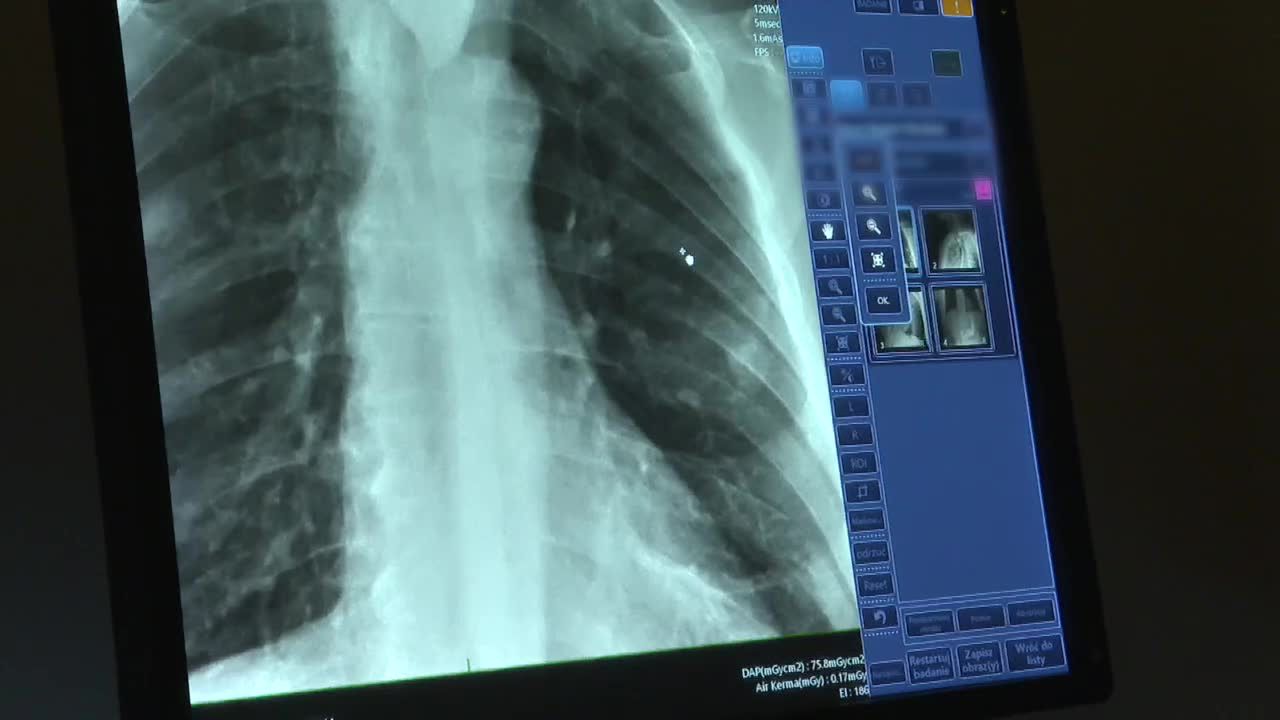

32. Finał Wielkiej Orkiestry Świątecznej Pomocy już 28 stycznia. W tym roku Orkiestra zbiera na leczenie “płuc po pandemii”. Zgromadzone środki przeznaczone zostaną na zakup urządzeń dla oddziałów pulmonologicznych dla dzieci i dorosłych.

Dr Iwona Witkiewicz, pulmonolog ze szpitala wojewódzkiego w Szczecinie, podkreśla, że – mino epidemii koronawirusa – płuca wciąż są w pewnym sensie “nieobecne” w publicznym dyskursie na temat problemów zdrowotnych Polaków. Dlatego fakt, że w tym roku WOŚP stawia właśnie na płuca, może przypomnieć opinii publicznej zarówno o chorobach płuc, jak i o cierpiących na nie, na ogół seniorach.